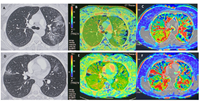

Experts Issue Guide on Lung Cancer Screening, Management During COVID-19

A new expert panel consensus statement published in the journals Radiology: Imaging Cancer, Chest and the Journal of the American College of Radiology provides guidance to clinicians managing lung cancer screening programs and patients with lung nodules during the COVID-19 pandemic.